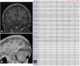

Familial occipital calcification and epilepsy